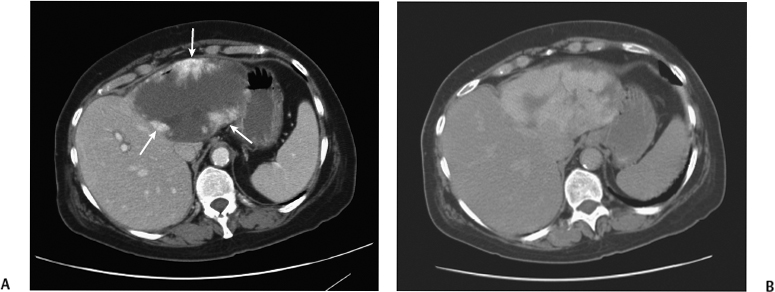

CT

要看清楚我们,CT检查是更清楚的。在CT下的我们,也是边界清楚的,呈低密度的肿块。大约10%的我们,可以同时发现里面有一些钙化灶。